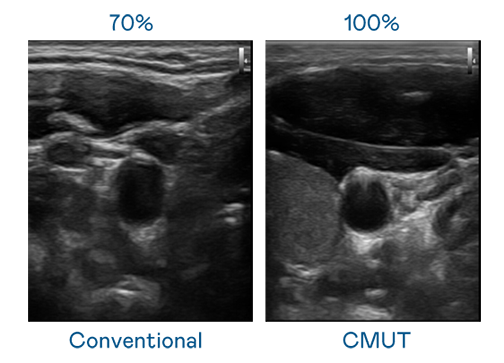

CMUT 技术是一种用电容式微机电元件来产生超音波讯号的技术。与传统 PZT 压电式技术相比,CMUT 频宽增加 30%,更宽频的超音波讯号让影像解析度大幅提升,是实现高影像品质医疗超音波扫描、促进精准医疗发展的关键技术。

超音波影像的解析度高低,首先取决于探头能发出的讯号频宽。星空体育app官网入口 CMUT 可提供高清晰的超音波讯号,提供高频宽、高灵敏度、影像纹理细节更高的超音波影像,协助医护人员缩短影像判读时间及利用精准的医疗影像进行诊断。